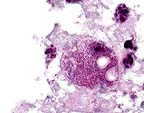

Multiple eosinophilic intracytoplasmic inclusion bodies (Negri bodies) in the cells of the Purkinje layer in the cerebellum of a 6-month old foal. (HE, 400X, 59K)

In the cerebrum, occasional vessels are surrounded by thin perivascular cuffs of lymphocytes. The cerebral cortex is mildly hypercellular (glial cells) and occasional neurons contain eosinophilic intracytoplasmic inclusion bodies that vary from 2-7 æm in diameter. In sections of cerebellum there is segmental loss of Purkinje cells; many remaining Purkinje cells contain single to multiple eosinophilic inclusions similar to those seen in cortical neurons.

Histologically, rabies infection is characterized by a nonsuppurative encephalomyelitis and ganglioneuritis with intraneuronal eosinophilic inclusion bodies (Negri bodies). The typical reaction is perivascular cuffing, gliosis and neuronal degeneration. The microscopic findings can vary greatly from case to case and from species to species with carnivores generally showing a more severe reaction than herbivores. In this case, inflammation is minimal. Negri bodies are generally 2-8 mm, discrete to amorphous inclusions with a clear, thin halo that range from none to several per cell. The location of neurons that contain Negri bodies is important and differs with the species of animal affected. Generally, the hippocampus is the most common site for finding Negri bodies in carnivores, whereas the Purkinje cells of the cerebellum are most often affected in herbivores and humans. Negri bodies have also been found in ganglion cells of the adrenal medulla, retina, and salivary gland. In some species, care must be taken to differentiate Negri bodies from nonspecific inclusions that have been found in the pyramidal cells of the hippocampus or the lateral geniculate nucleus neurons in cats, skunks, and dogs and in the larger neurons of the medulla and spinal cord of old sheep and cattle; these inclusions are often smaller than Negri bodies. Dogs also may have cytoplasmic lamellar bodies in neurons of the thalamus and cerebellar cortical Purkinje cells.